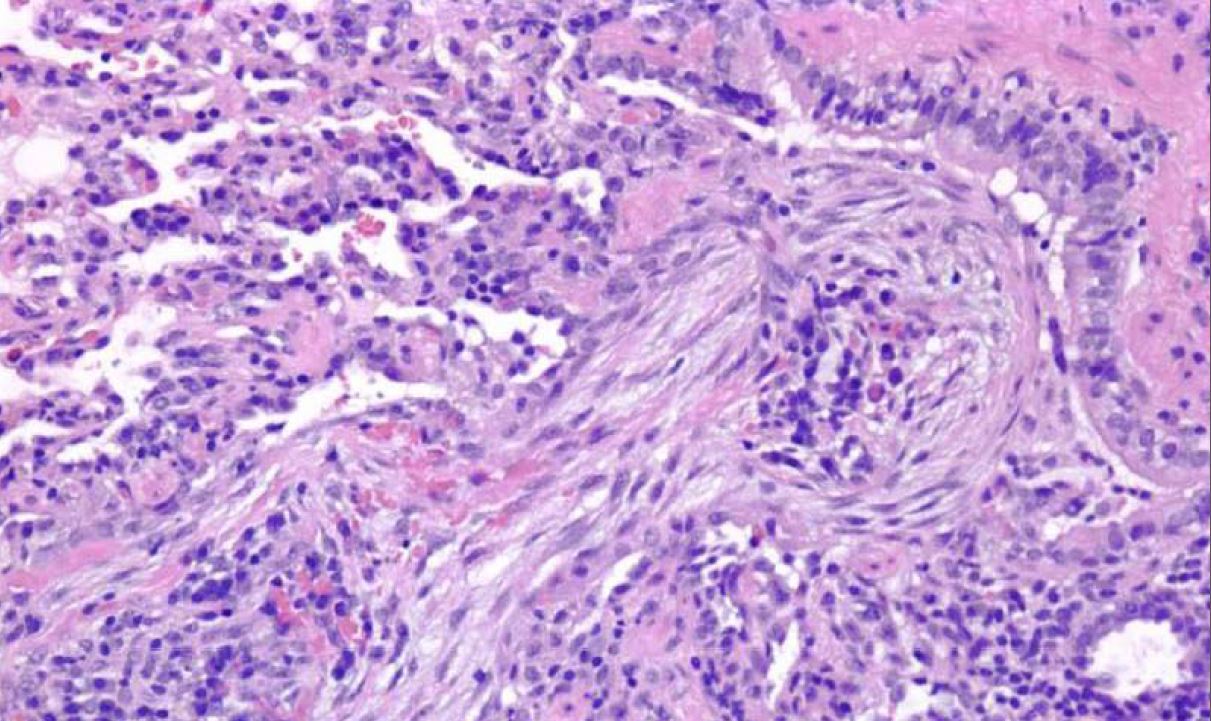

Capillaritis

Evidence of diffuse pulmonary hemorrhage

DDX: Goodpasture, Microscopic polyangiitis, Lupus, Wegener’s, mixed cryoglobulinemia, Henoch-Schonlein purpura and antiphospholipid syndrome